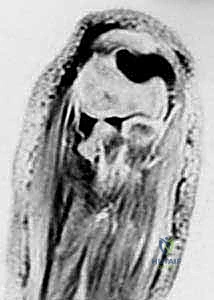

3. التصوير المقطعي المحوسب (CT Scan)

في حالات الكسور المتفتتة المعقدة (مثل ميسون النوع الثالث)، أو عند التخطيط لعملية جراحية دقيقة تتطلب إعادة بناء المفصل، يطلب الدكتور هطيف إجراء تصوير مقطعي ثلاثي الأبعاد. يوفر هذا التصوير خريطة دقيقة لحجم وموقع كل قطعة عظمية، مما يسهل اختيار نوع الشرائح والمسامير المناسبة.

4. التصوير بالرنين المغناطيسي (MRI)

لا يُطلب بشكل روتيني لكسور العظام، ولكنه يُستخدم إذا كان هناك اشتباه قوي في تمزق الأربطة المحيطة بالمرفق (مثل الرباط الجانبي الزندي أو الرباط الحلقي) أو إصابة الغضاريف المفصلية.